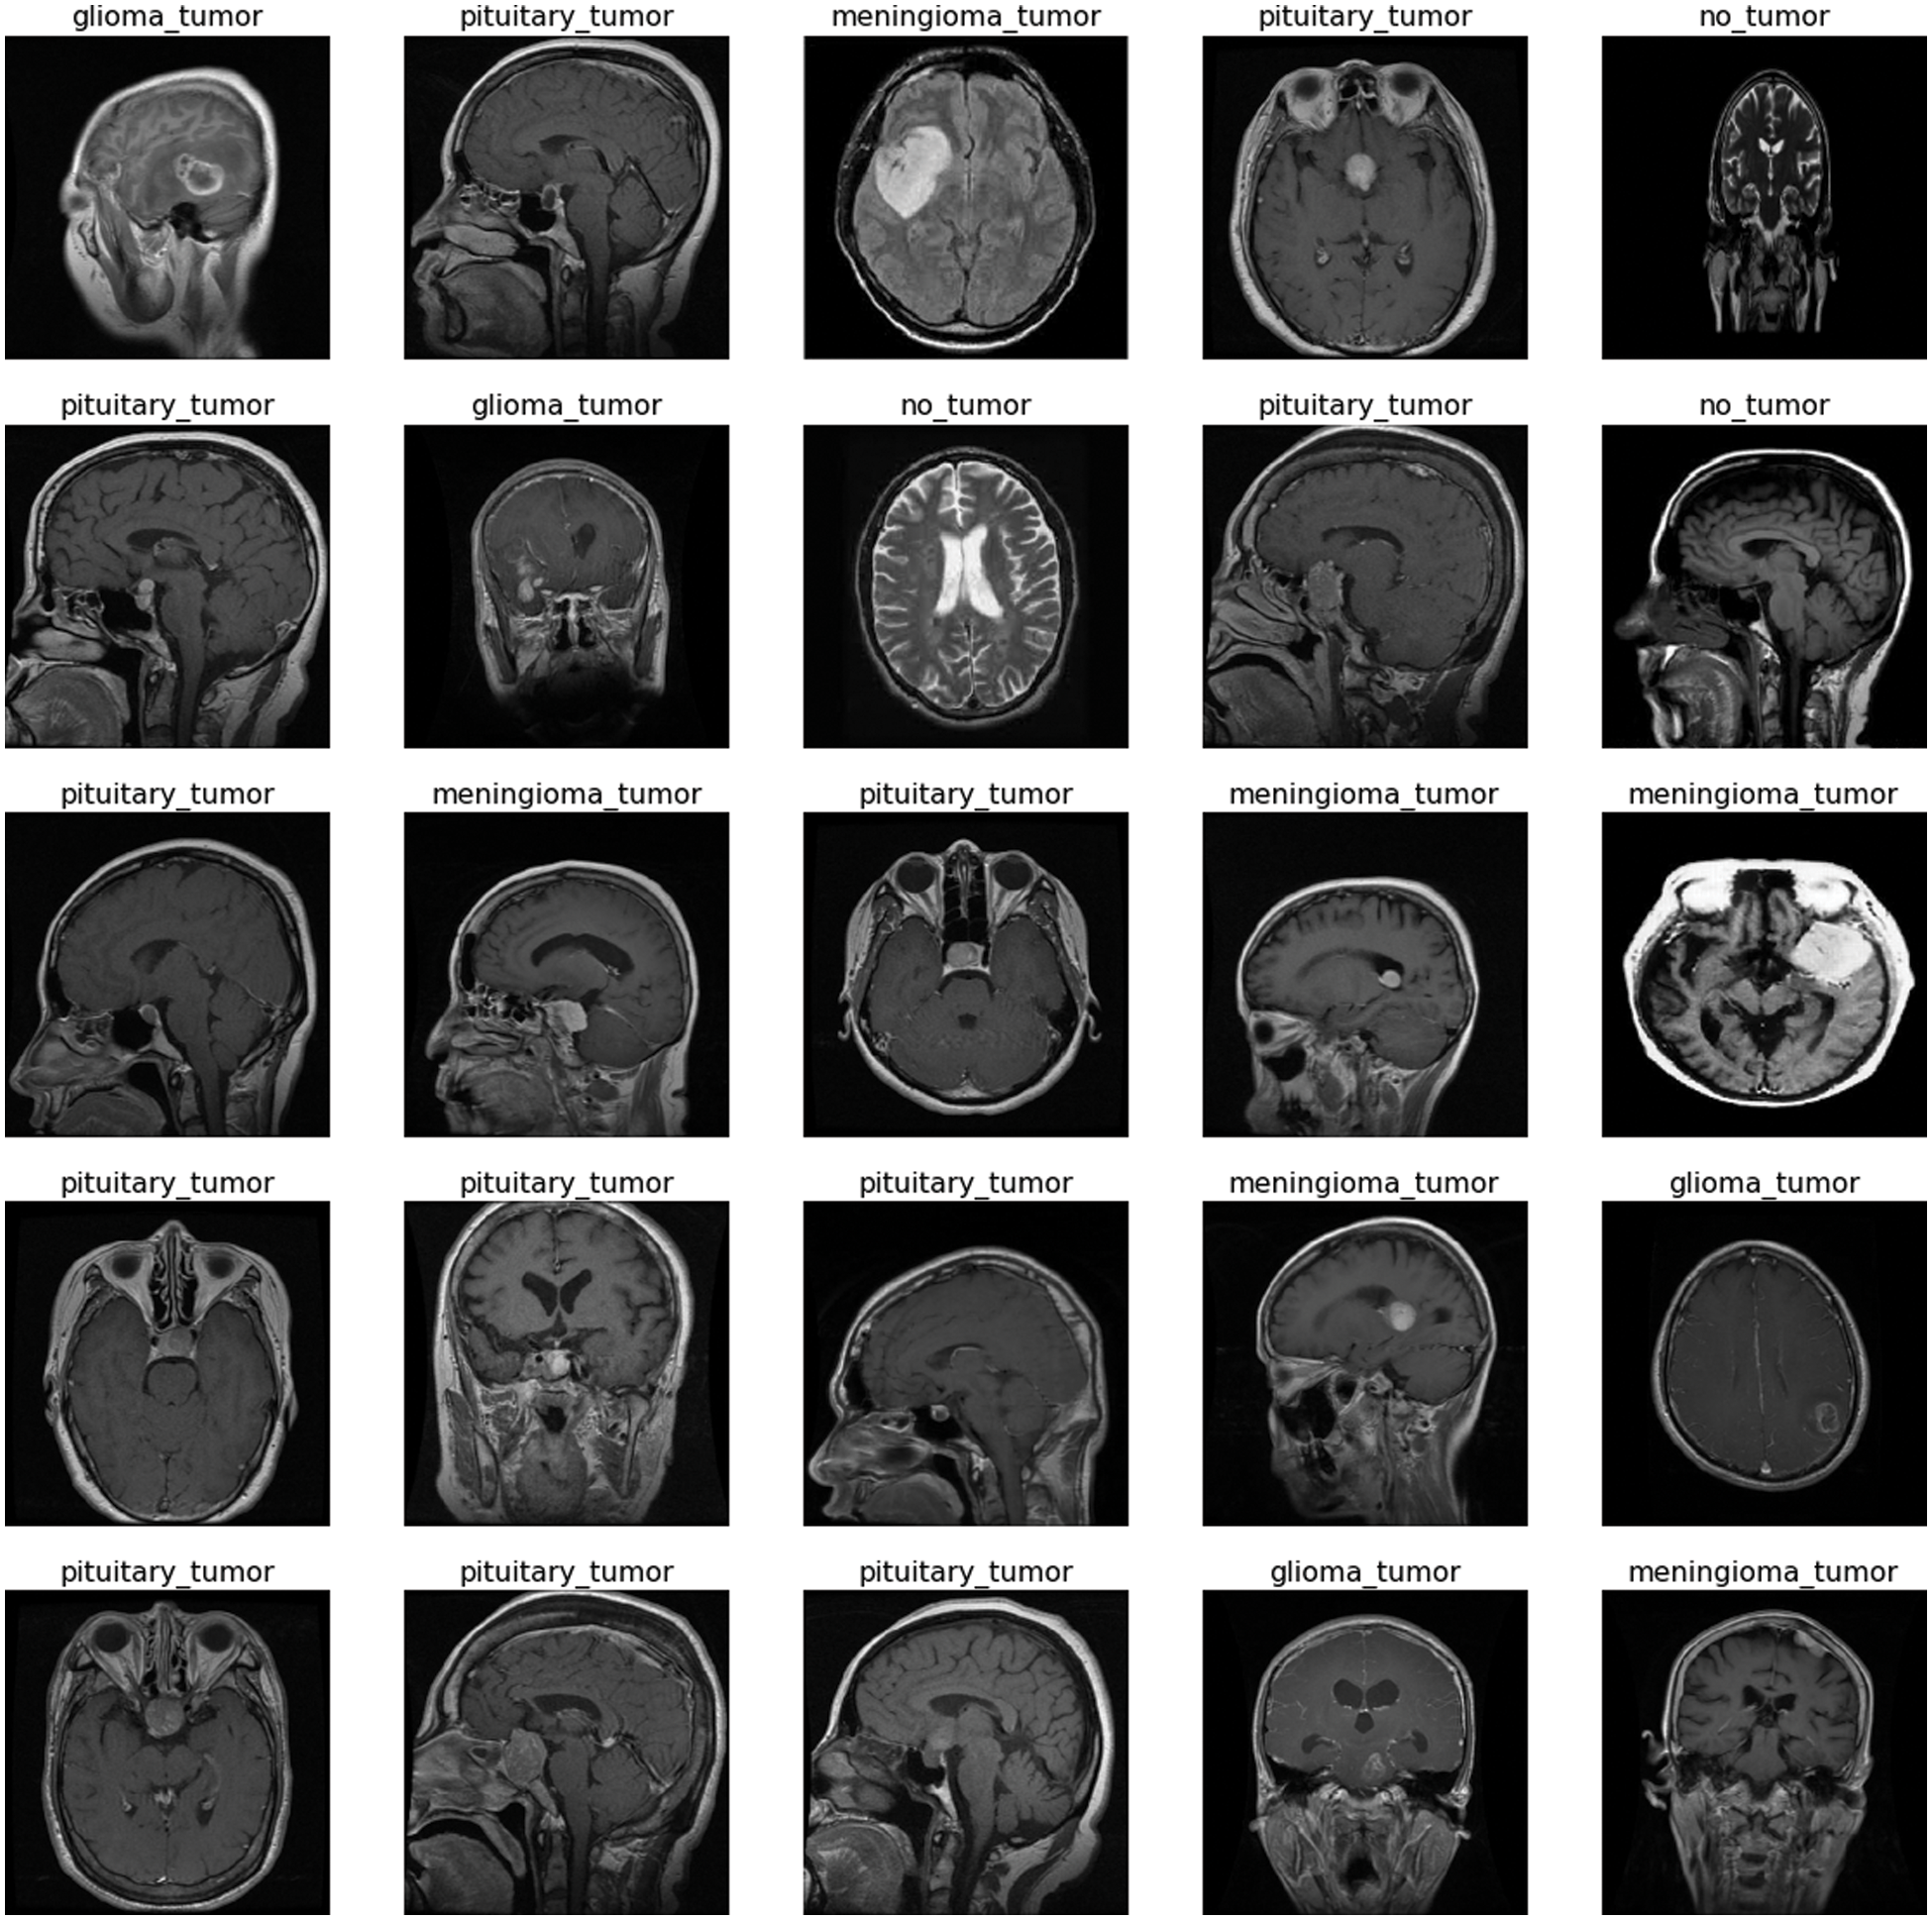

To overcome the problem of deploying CNN on a limited dataset, deep learning offers a transfer learning approach. It is based on two scenarios (i) fine-tune the Convolutional Network (ConvoNet) and (ii) freeze the Convolutional Network (ConvoNet) layers. Transfer learning approaches are applied to both large and small datasets named base and training datasets. At first, the information is gained by implementing the CNN on a large dataset which is a pre-trained network; then, the resulting information acts as input and is transferred to a small dataset [10]. This technique is called fine-tuning. The used dataset consists of four tumor classes glioma, meningioma, pituitary, and No Tumor [11], as shown in Fig. 1. A glioma tumor is a common brain tumor that originates in the glial tissues surrounded by neurons [12]. In contrast, meningioma is a tumor that arises from meninges tissues surrounding the brain and spinal cardinal system [13]. A pituitary tumor is due to the abnormal growth of pituitary glands in the back of the nose [14]. Transfer learning is adopted to fine-tune the information retrieved from a base dataset. In fine-tuning, weights of pre-trained networks based on large datasets are transferred by the transfer learning approach to the desired network, which must be trained on a small dataset [15].

Figure 1: Each category’s proportion of the contrast-enhanced magnetic resonance imaging (CE-MRI) dataset

The freely accessible CE-MRI dataset (https://figshare.com/articles/dataset/brain_tumor_dataset/1512427) has been used in this work. The dataset consists of 2-dimensional images with a large slice gape. The dataset was collected from 2005 to 2020 from different hospitals in China. The dataset consists of four tumor classes glioma, meningioma, pituitary, and no tumor as shown in Fig. 1. A glioma tumor is a common brain tumor that originates in the glial tissues surrounded by neurons. In contrast, meningioma is a tumor that arises from meninges tissues surrounding the brain and spinal cardinal system. A pituitary tumor is due to the abnormal growth of pituitary glands in the back of the nose. The size of each image in the dataset is 512 x 512 pixels, as shown in Fig. 2. The CE-MRI dataset was separated into training 70%, validation 15%, and testing 15% to train the BW-VGG19 model for brain tumor segmentation. The description of the dataset is given below in Tab. 1.

Figure 2: Sample images of contrast-enhanced magnetic resonance imaging (CE-MRI) dataset